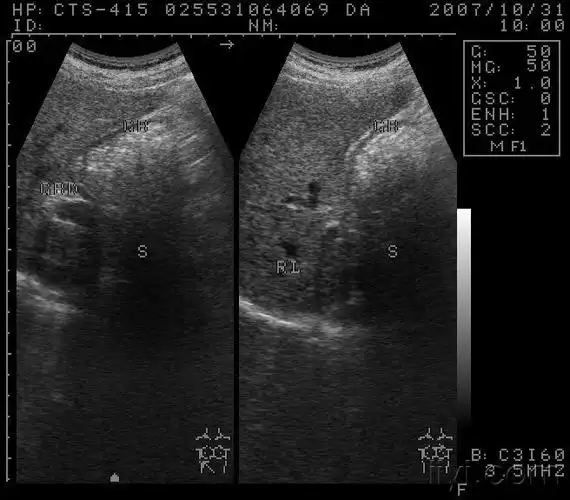

胆囊充满型结石? - 超声医学讨论版 - 爱爱医医学论坛